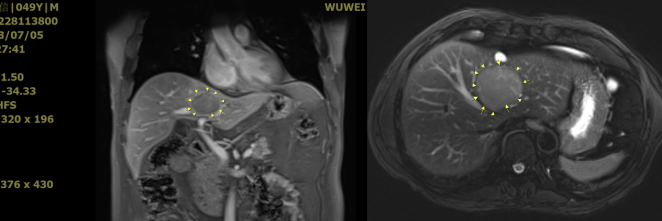

【病例五】男性,49岁,肝门部肝细胞癌。我们利用武威重离子特有的HFOV技术解决呼吸动度问题,精准处理了夹在门脉和胆管中央的肿瘤,治疗后肿瘤迅速消失。

wuwei

左侧为2023年7月重(碳)离子治疗前,右图为重(碳)离子治疗后。重(碳)离子治疗后肿瘤迅速消失,见纤维组织,治疗中患者无任何不适,肝功能始终保持正常。截止发稿日,重(碳)离子治疗后26个月,患者肿瘤完全消失,体力状况良好,生活完全正常。